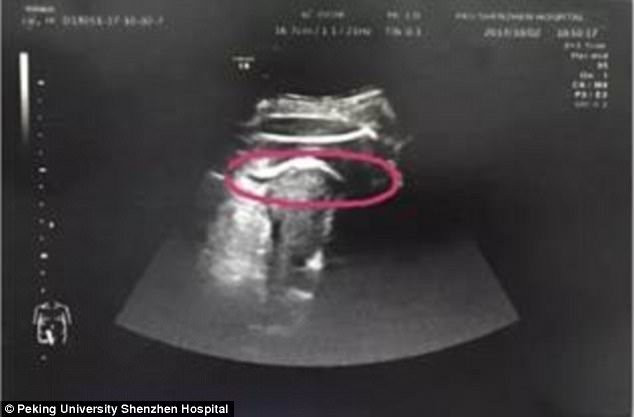

Hình ảnh siêu âm cho thấy tử cung của sản phụ bị thai nhi đạp rách. (Ảnh: Daily Mail)

Kết quả siêu âm cho thấy, tử cung bị rách như các bác sỹ phỏng đoán và nguyên nhân do thai nhi 35 tuần tuổi đạp vỡ. Đứa trẻ thậm chí còn thò chân sang khoang bụng khiến đùi bị mắc kẹt ở thành tử cung.